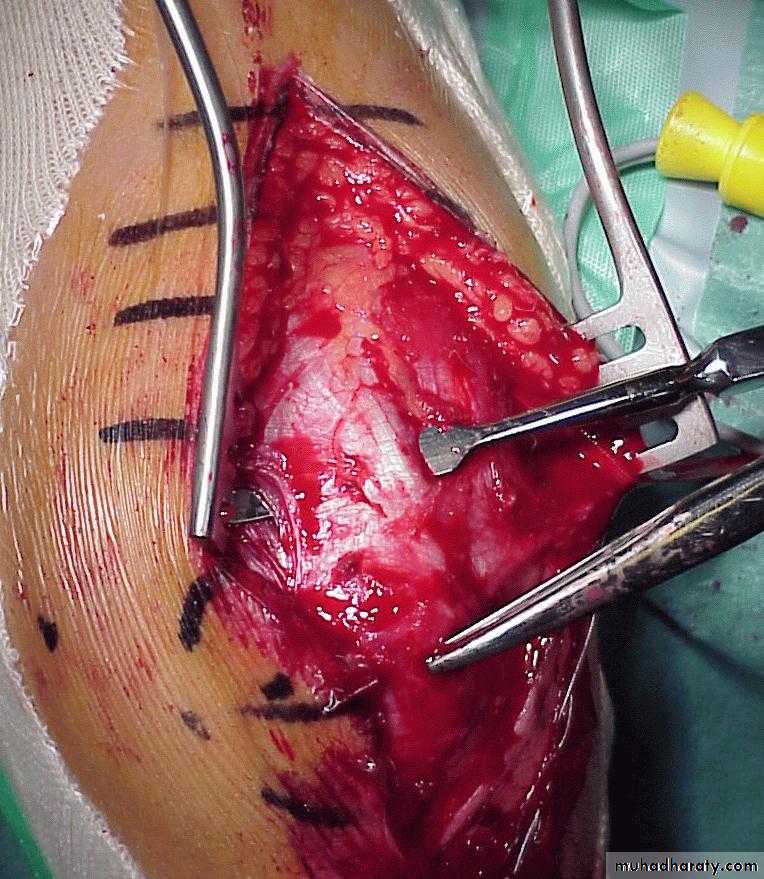

past the impaled fragment.In those irreducible fractures, what dictates the preferred surgical approach?

Anteromedial incision

Anterolateral Incision

The ability to visualize

the interposed vital structures is essential.Post-Lat Fracture:

Post-Medial Fracture

Medial humeral

spike

Lateral humeral

spikeWhat about the posterior approach?

The posterior

tricepssplitting

approach

Advantages:

Easy approach

Direct

visualization

of fracture site

Disadvantages:

Injures virgin

tissue

Unable to

visualize

anterior A. & N.

*Compliments of Jamie Maclean(Pearth ,Scotland)